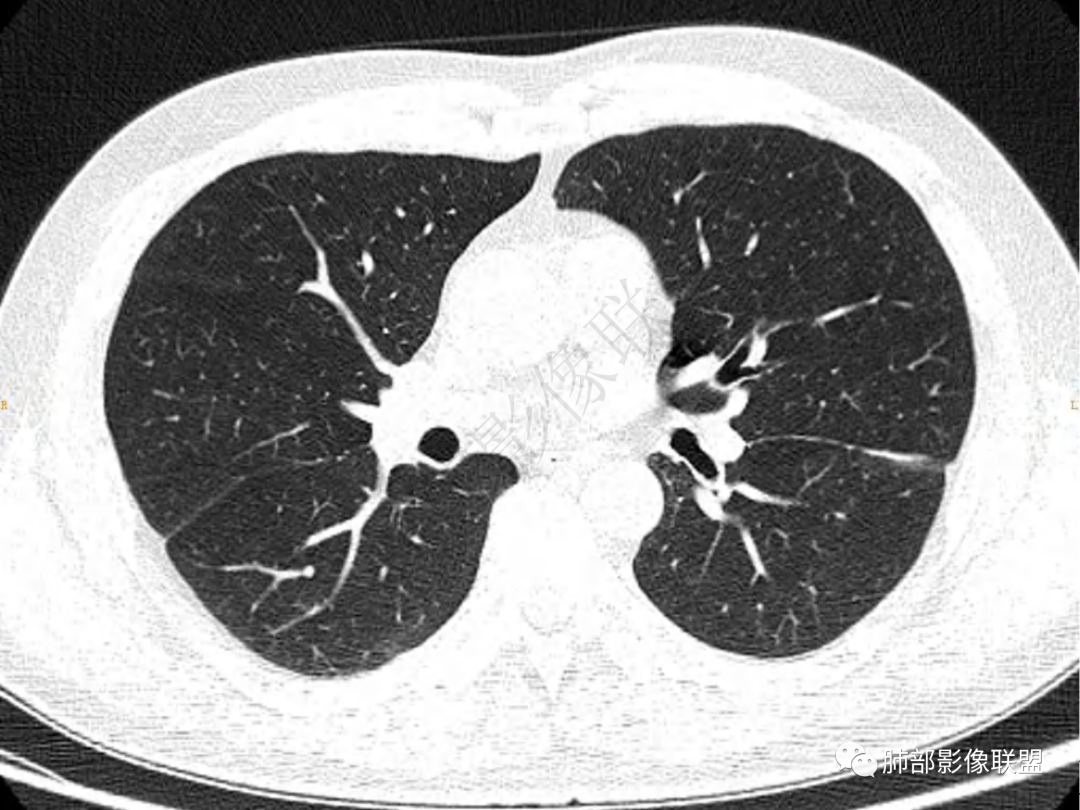

1.中年男性,咳嗽咳痰20余天,间断咯血2周

2.左肺下叶团片影,跨背段及内前基底段,实性部分类椭圆形,密度不甚均匀,可见毛刺及棘状突起,未见典型分叶及胸膜凹陷。病灶上下缘可见相应肺段支气管旁进侧出,管壁轻度增厚,未见狭窄阻塞。

3.周边较大范围磨玻璃影,边界相当模糊,小叶增厚明显。注意叶裂另一侧、左肺舌段亦可见磨玻璃影及增厚的小叶间隔。未见明确卫星病灶。

4.实性部分不均匀环形强化并显示一小范围低密度坏死区或空洞。较之肺窗,整体纵隔窗范围较小,提示病灶并不十分密实。抑或为不同时段图像。

5.双肺门及纵隔未见增大淋巴结。未见胸腔积液。